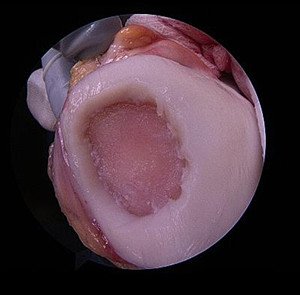

Bei der Technik der Mikrofrakturierung werden nach Defektpräparation in den freiliegenden Knorpel kleine Löcher (Abbildung) eingebracht (mittels Bohrer oder Ale). Aus diesen Löchern gelangt Blut aus dem Knochen in die präparierte Defektregion und setzt sich dort ab. Das Blut aus dem Knochen besitzt einen gewissen Anteil an Stammzellen. Diese Stammzellen sind dazu in der Lage, sich in verschiedene Gewebe umzuwandeln, unter anderem in Knorpel. Diesen Differenzierungsweg macht man sich bei der Technik der Mikrofrakturierung zu Nutze. Diese Technik wird arthroskopisch realisiert und ist damit von geringer Invasivität. Sie kann lediglich bei reinen Knorpelschäden angewendet werden, welche zugleich nicht grösser als 2.5cm2 sind. Diese Technik wird immer rein arthroskopisch, also in Schlüssellochtechnik durchgeführt.